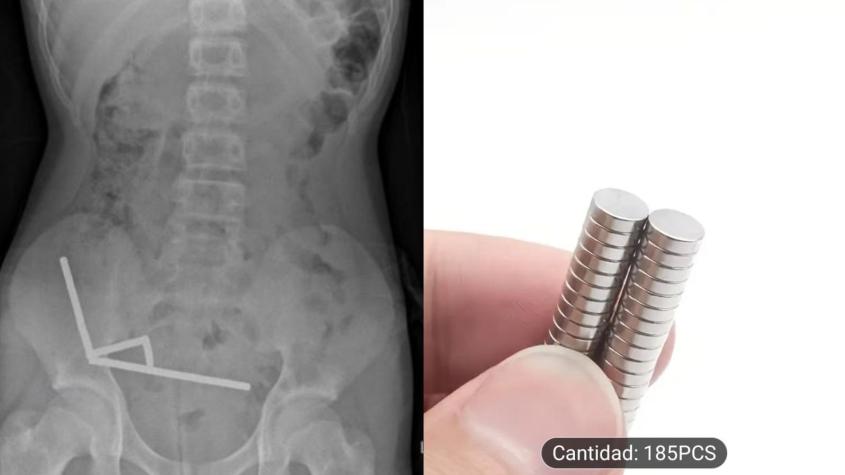

Niño tuvo que ser operado tras tragarse 100 imanes comprados por internet en Nueva Zelanda